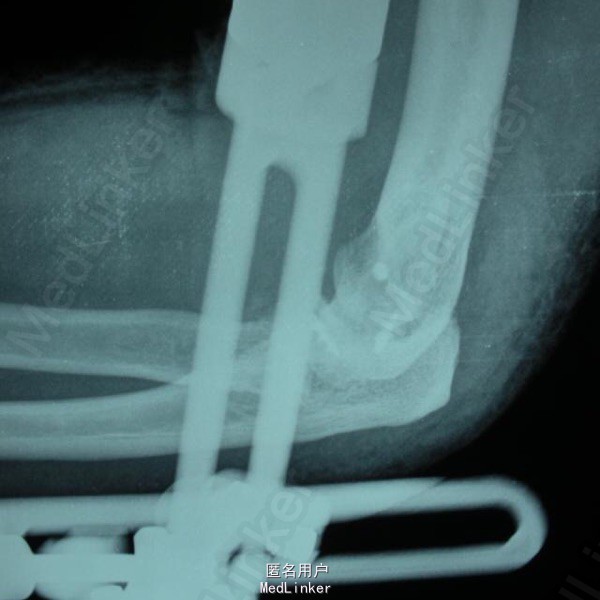

手法复位后X片及术后正侧位 初步诊断:左肘关节损伤三联征。治疗过程:尺骨冠状突骨折块复位固定、桡骨小头骨折块复位固定、内外侧副韧带修复、可活动式外固定支架固定。

对于术后选择石膏固定还是铰链式外固定支架固定,主要考虑哪种外固定有利于术后功能恢复。肘关节损伤三联征主要的并发症:僵硬,复发性不稳定,异位骨化。避免僵硬发生的有效手段就是术后即可以活动(主动或被动)肘关节,石膏固定显然不能达到术后即开始活动肘关节,如果用石膏固定最短需要 2 周(有人建议 7~10 天),如果骨折固定较稳定,没有再移位或复发脱位的倾向,2 周时间是可以的,如果有骨折再移位或复发脱位的倾向,2 周时间可能不够,需延长至 4 周或 6 周。 此时肘关节才能开始活动,僵硬的机会已很大。铰链式外固定支架固定后,患者术后次日即可以主动活动肘关节,也可被动活动,同时外固定支架可施加牵引力有效保护冠状突及桡骨头骨折不再移位,保护修复后的内外侧副韧带复合体不被牵拉撕裂,关节复发脱位不再出现。 去掉外固定架的时间取决于肘关节的稳定性、骨折愈合情况、关节活动度增加和针道状况等。外固定架固定肱尺关节 3~6 周,有人建议外固定架平均使用时间为 8 周 (6—10 周)。术后 8 周后允许非限制性的关节活动锻炼。